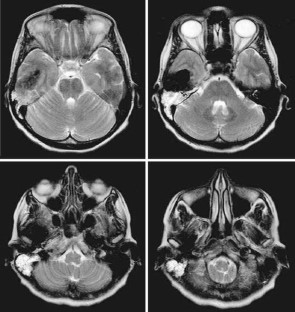

Central giant cell granuloma is a benign intraosseous lesion that most commonly occurs in the facial bones. Its location in the temporal bone is extremely rare and only 20 cases have been reported in the literature. We report a case of an adult female patient presenting with a right serous otitis media and mastoiditis associated with a mixed hearing loss during 6 months. CT-scan and MRI revealed a temporal bone tumor involving the mastoid, and surrounding the right temporo-mandibular joint. Tumor was totally removed after a canal-wall-down mastoidectomy and middle ear exclusion. Pathology revealed a central giant cell granuloma. Seven months following the surgery there was no evidence of recurrence. Central giant cell granuloma is a rare temporal bone lesion, with non specific clinical and imaging signs but characteristic pathological features. Today, a total surgical removal and regular MRI follow-up is the best management option.

Fig. 1

Fig. 2

Fig. 3

Fig. 4